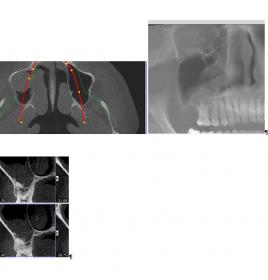

Nach immer weiteren Beschwerden wechselte ich den Kieferchiruge, da ich einen starken Druck auf dem rechten Oberkiefer hatte der in das Gesicht ausstrahlte. OP des neuen Chirurgen, nach Aufklärungsgespräch, war am 5. Januar indem eine ca 1.5-2cm große Fensterung über 16 angelegt wurde, da eine entzundene Kieferhöhlenzyste festgestellt wurde. Nach pathologischem Bericht, den ich auch erhalten habe, war die Zyste 3cm groß und eine mäßig-gradige Entzündung der Kieferhöhle. Der Chirurg meinte es könne Monate dauern zur vollständigen Heilung und bei mir wurde jetzt auch schon viel herumgeschnitten. Nach 5 Wochen habe ich mich nochmals vorgestellt da der Druck/Brennen noch anhält besonderes gegen Nachmittag/Abend und auch teilweise richtig stark wird. Vor der OP konnte ich kaum an meinen Knochen/Zahnfleisch über den Zähnen fassen, da der Bereich wegen der Entzündung geschmerzt hat, nun ist das ohne Probleme möglich. Er meinte ich solle mir keine Gedanken machen er habe einige Patienten die gerade nach solchen chronischen langwierigen Entzündungen rückläufige Beschwerden haben bis zu 3-6 Monate, und meine Entzündung war nicht ohne. Nun sind 7 Wochen vergangen und wenn ich mein Gesicht ruhig halte schmerzt es immer noch mittelstark. Ich weiß die Schmerzen können von mehreren Faktoren kommen und es gibt auch Trigeminus, atypisch, Muskel usw was er erstmal alles ausschließt. Muskel schmerzt nicht beim hindrücken und die Entzündung war ja wirklich da. Lymphknoten sind auch komplett abgeschwollen (die waren 10 Wochen dick). Was sagen Sie abgesehen von anderen Diagnosen, die noch sein könnten, “darf” das nach 7 Wochen noch mittelstark schmerzen (Von dieser OP und Entzündung)? Ich weiß Schmerz empfindet jeder anders und man kann darüber eig keine Aussage treffen daher das “darf”. Anbei ein DVT Screenshot von dem 2ten Chirurgen vor der OP, davor wurde schon eine 1,2cm Zyste über Zahn 17 entfernt. Meinem aktuellen Chirurgen vertraue ich eig. sehr, ich wollte nur nochmals eine zweite Meinung.

[ATTACH=CONFIG]1459[/ATTACH][ATTACH=CONFIG]1460[/ATTACH]

Vielleicht hatten Sie eine nicht dentogene Sinusitis und nun eine iatrogene Sinusitis – also vom Arzt verursacht … senden Sie mir lieber das Bild, welches als Entscheidungsgrund galt für die OP.